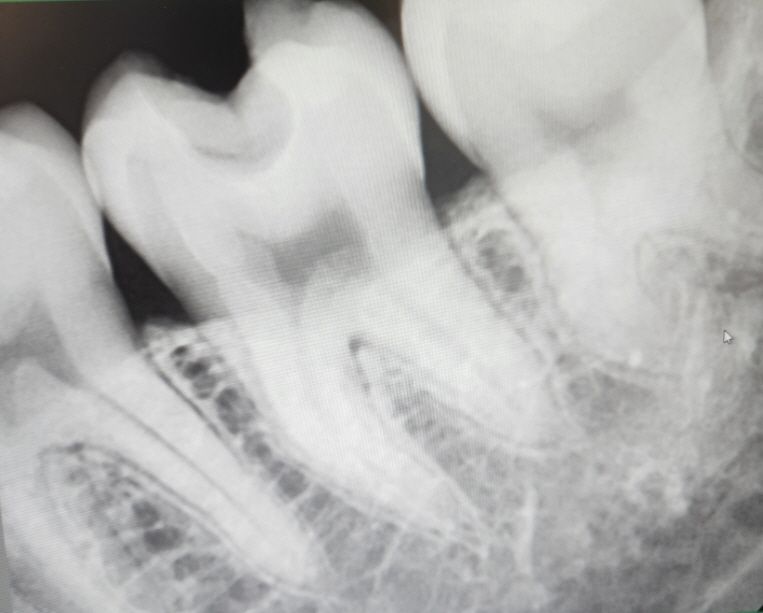

사진은 왼쪽 볼쪽으로 찍은 엑스레이입니다

엑스레이 상으로는 충치가 그렇게 깊어 보이진 않지만, 아마 육안상에 보이는 충치를 제거하다보면 신경이 노출될수도 있다는 이야기 같습니다.

파란색이 치앗니경, 빨간색이 이차충치, 노란색이 파절된 아말감입니다.

육안으로 보이는 검은 것은 아말감 변색을 확률이 높습니다만 방사선 사진상 이차충치가 있을 확률이 높습니다